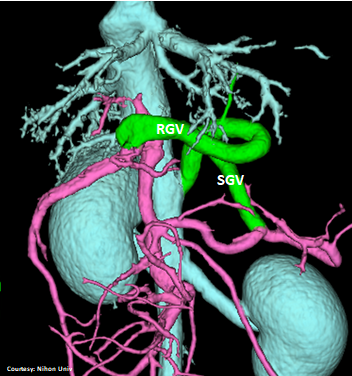

Does the RIGHT GASTRIC VEIN (RGV) contribute blood to the shunt?

Does the SHORT GASTRIC VEIN (SGV) contribute blood to the shunt?

“LGC +RGV +SGV”

Left Gastro-Caval Shunt with Right Gastric Vein and Short Gastric Vein contributions

Courtesy: Nihon Univ